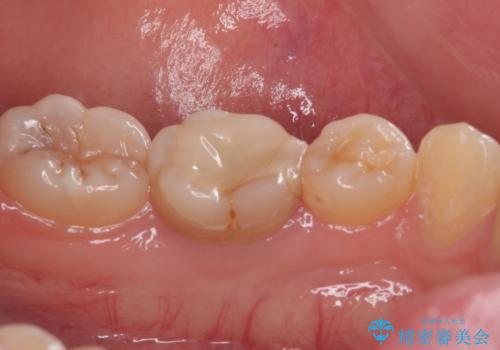

- 神経を取り除いた後に歯の色が変色して気になってきたとのことで来院された患者様です。

前歯は片側のみ神経を取り除かれていましたが、反対側もむし歯治療の詰め物が広範囲に及んでいたため、両方の歯をオールセラミッククラウンにて補綴治療を行うこととしました。

奥歯も著しく茶色に変色していたため、同様にオールセラミッククラウンにて補綴治療を行うこととしました。